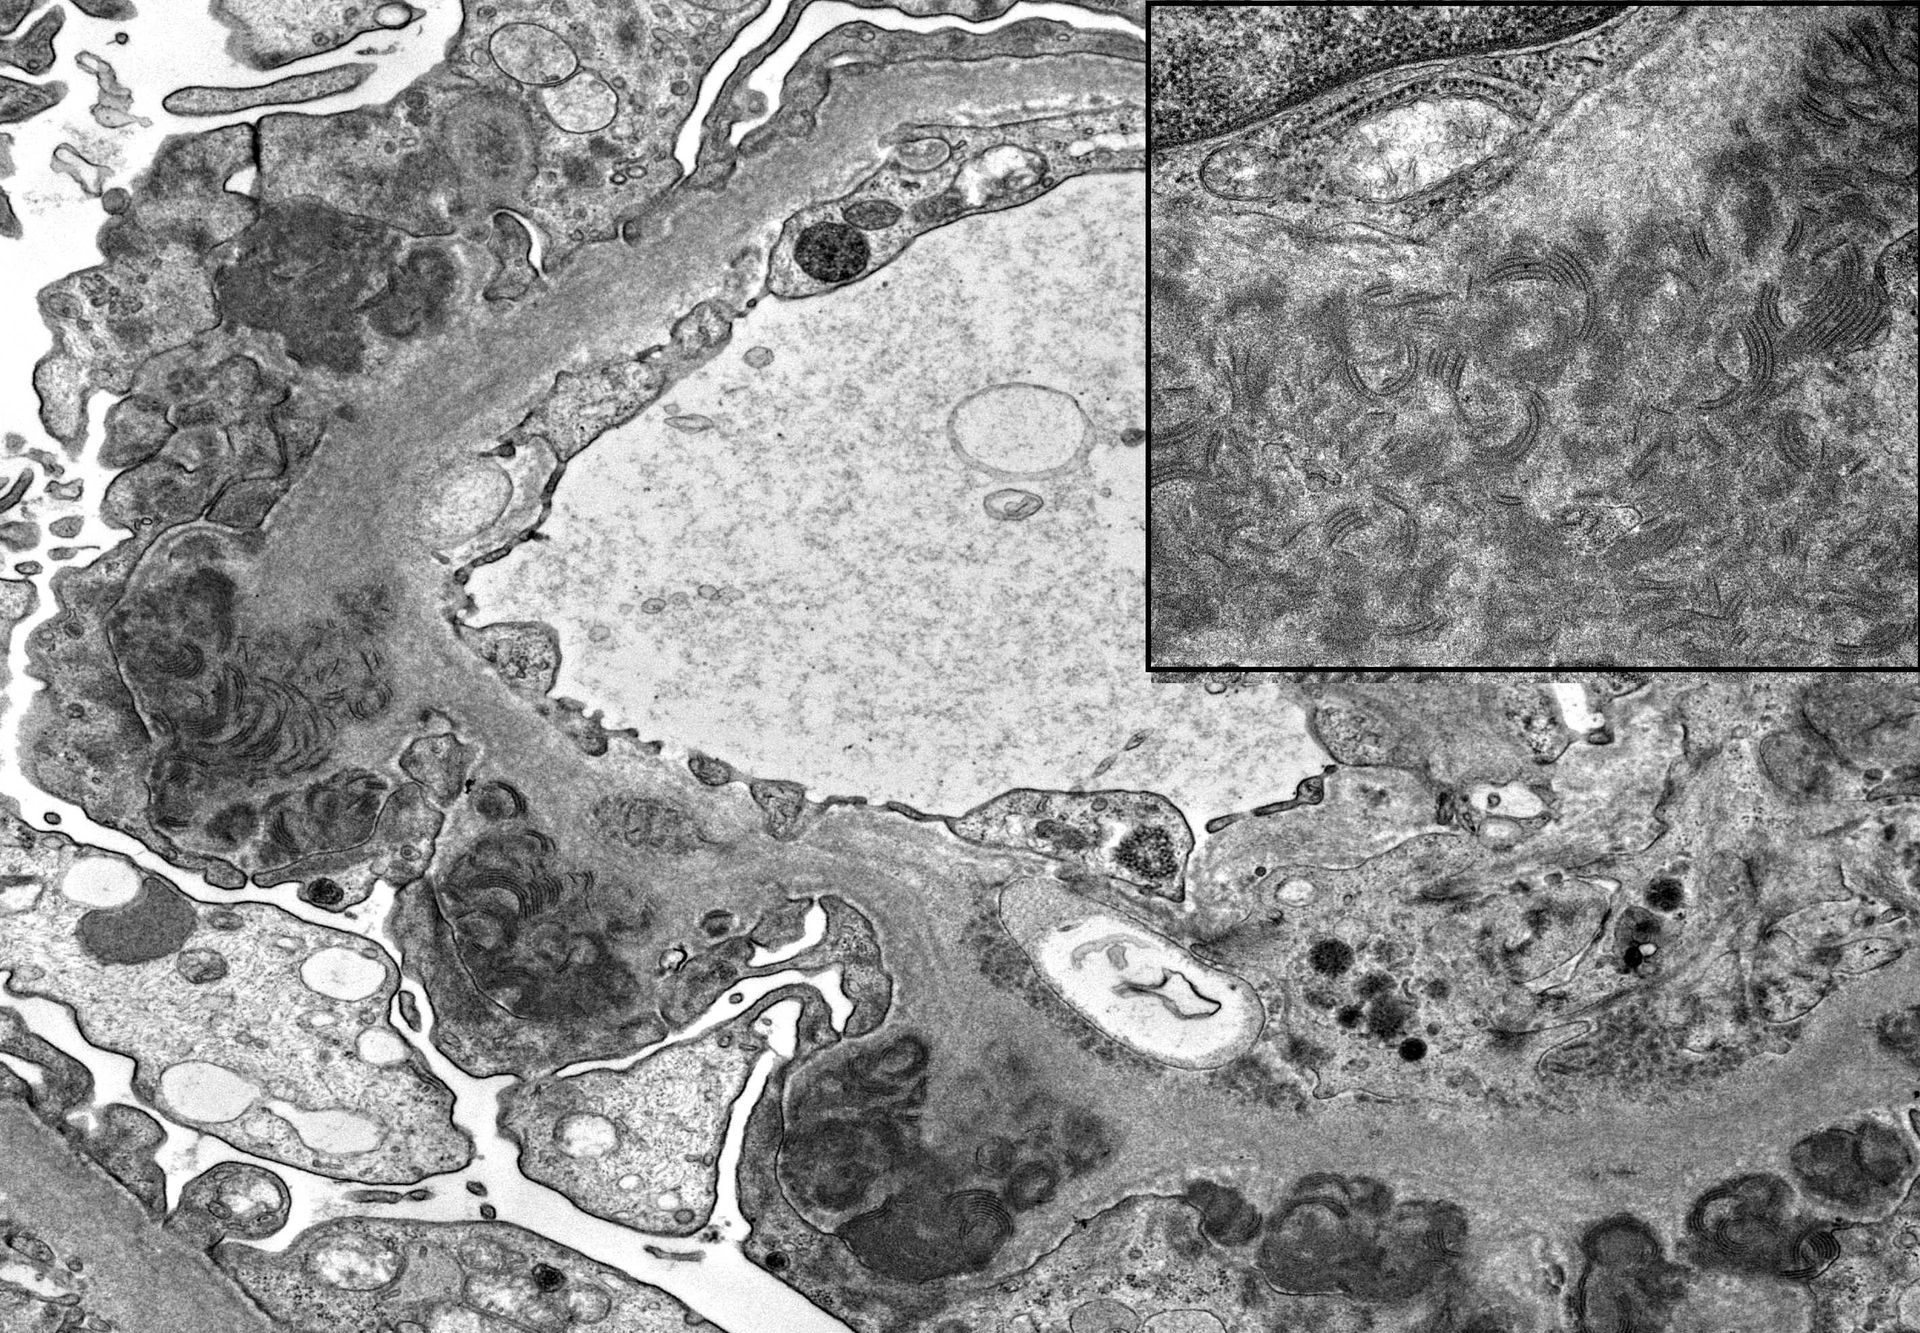

- Dijagnostički polutanki rezovi smole